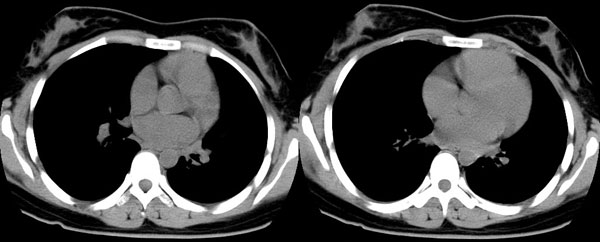

女性,25岁。反复咯血3年,再咯10天。外院x线胸片示:肺炎?支扩?

ct所见:左肺下叶基底段见大片状毛玻璃样改变,其内可见扩张细支气管。

ct所见:左肺下叶基底段见大片状毛玻璃样改变,其内可见扩张细支气管及血管纹理影。后接正常描述。

胸部ct平扫所见:胸廓两侧欠对称,左侧略小,胸壁骨质结构完整。左肺下叶后、外基底段

见大片状毛玻璃样淡薄影,边缘渐淡,其内可见多个环形小囊状影。余肺野清晰,

肺纹理规则,气管支气管通畅,内壁光滑。心脏、大血管大小、形态、密度未见

明显异常,胸膜不厚、光滑,纵隔内未见明显肿大淋巴结。

诊断意见:左肺下叶大片状毛玻璃样淡薄影考虑支气管扩张伴出血。